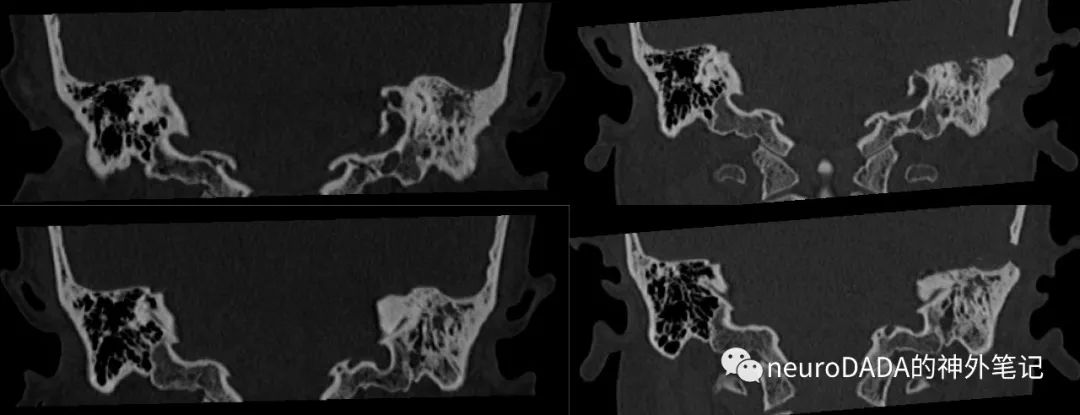

术后颞骨HRCT(左为术前,右为术后,同层面对比)

轴位(从上到下)

冠状位(从前到后)

根据HRCT,回过头来看术中磨除的骨质,证实一开始磨除的确实是上半规管上方的弓状隆起附近骨质,并向后扩展至颈静脉球上方、后半规管层面的骨质;耳蜗主要磨除了顶转和部分中转,底转保留;向前一直深入破裂孔后缘,切除了此部分受侵的岩尖骨质。